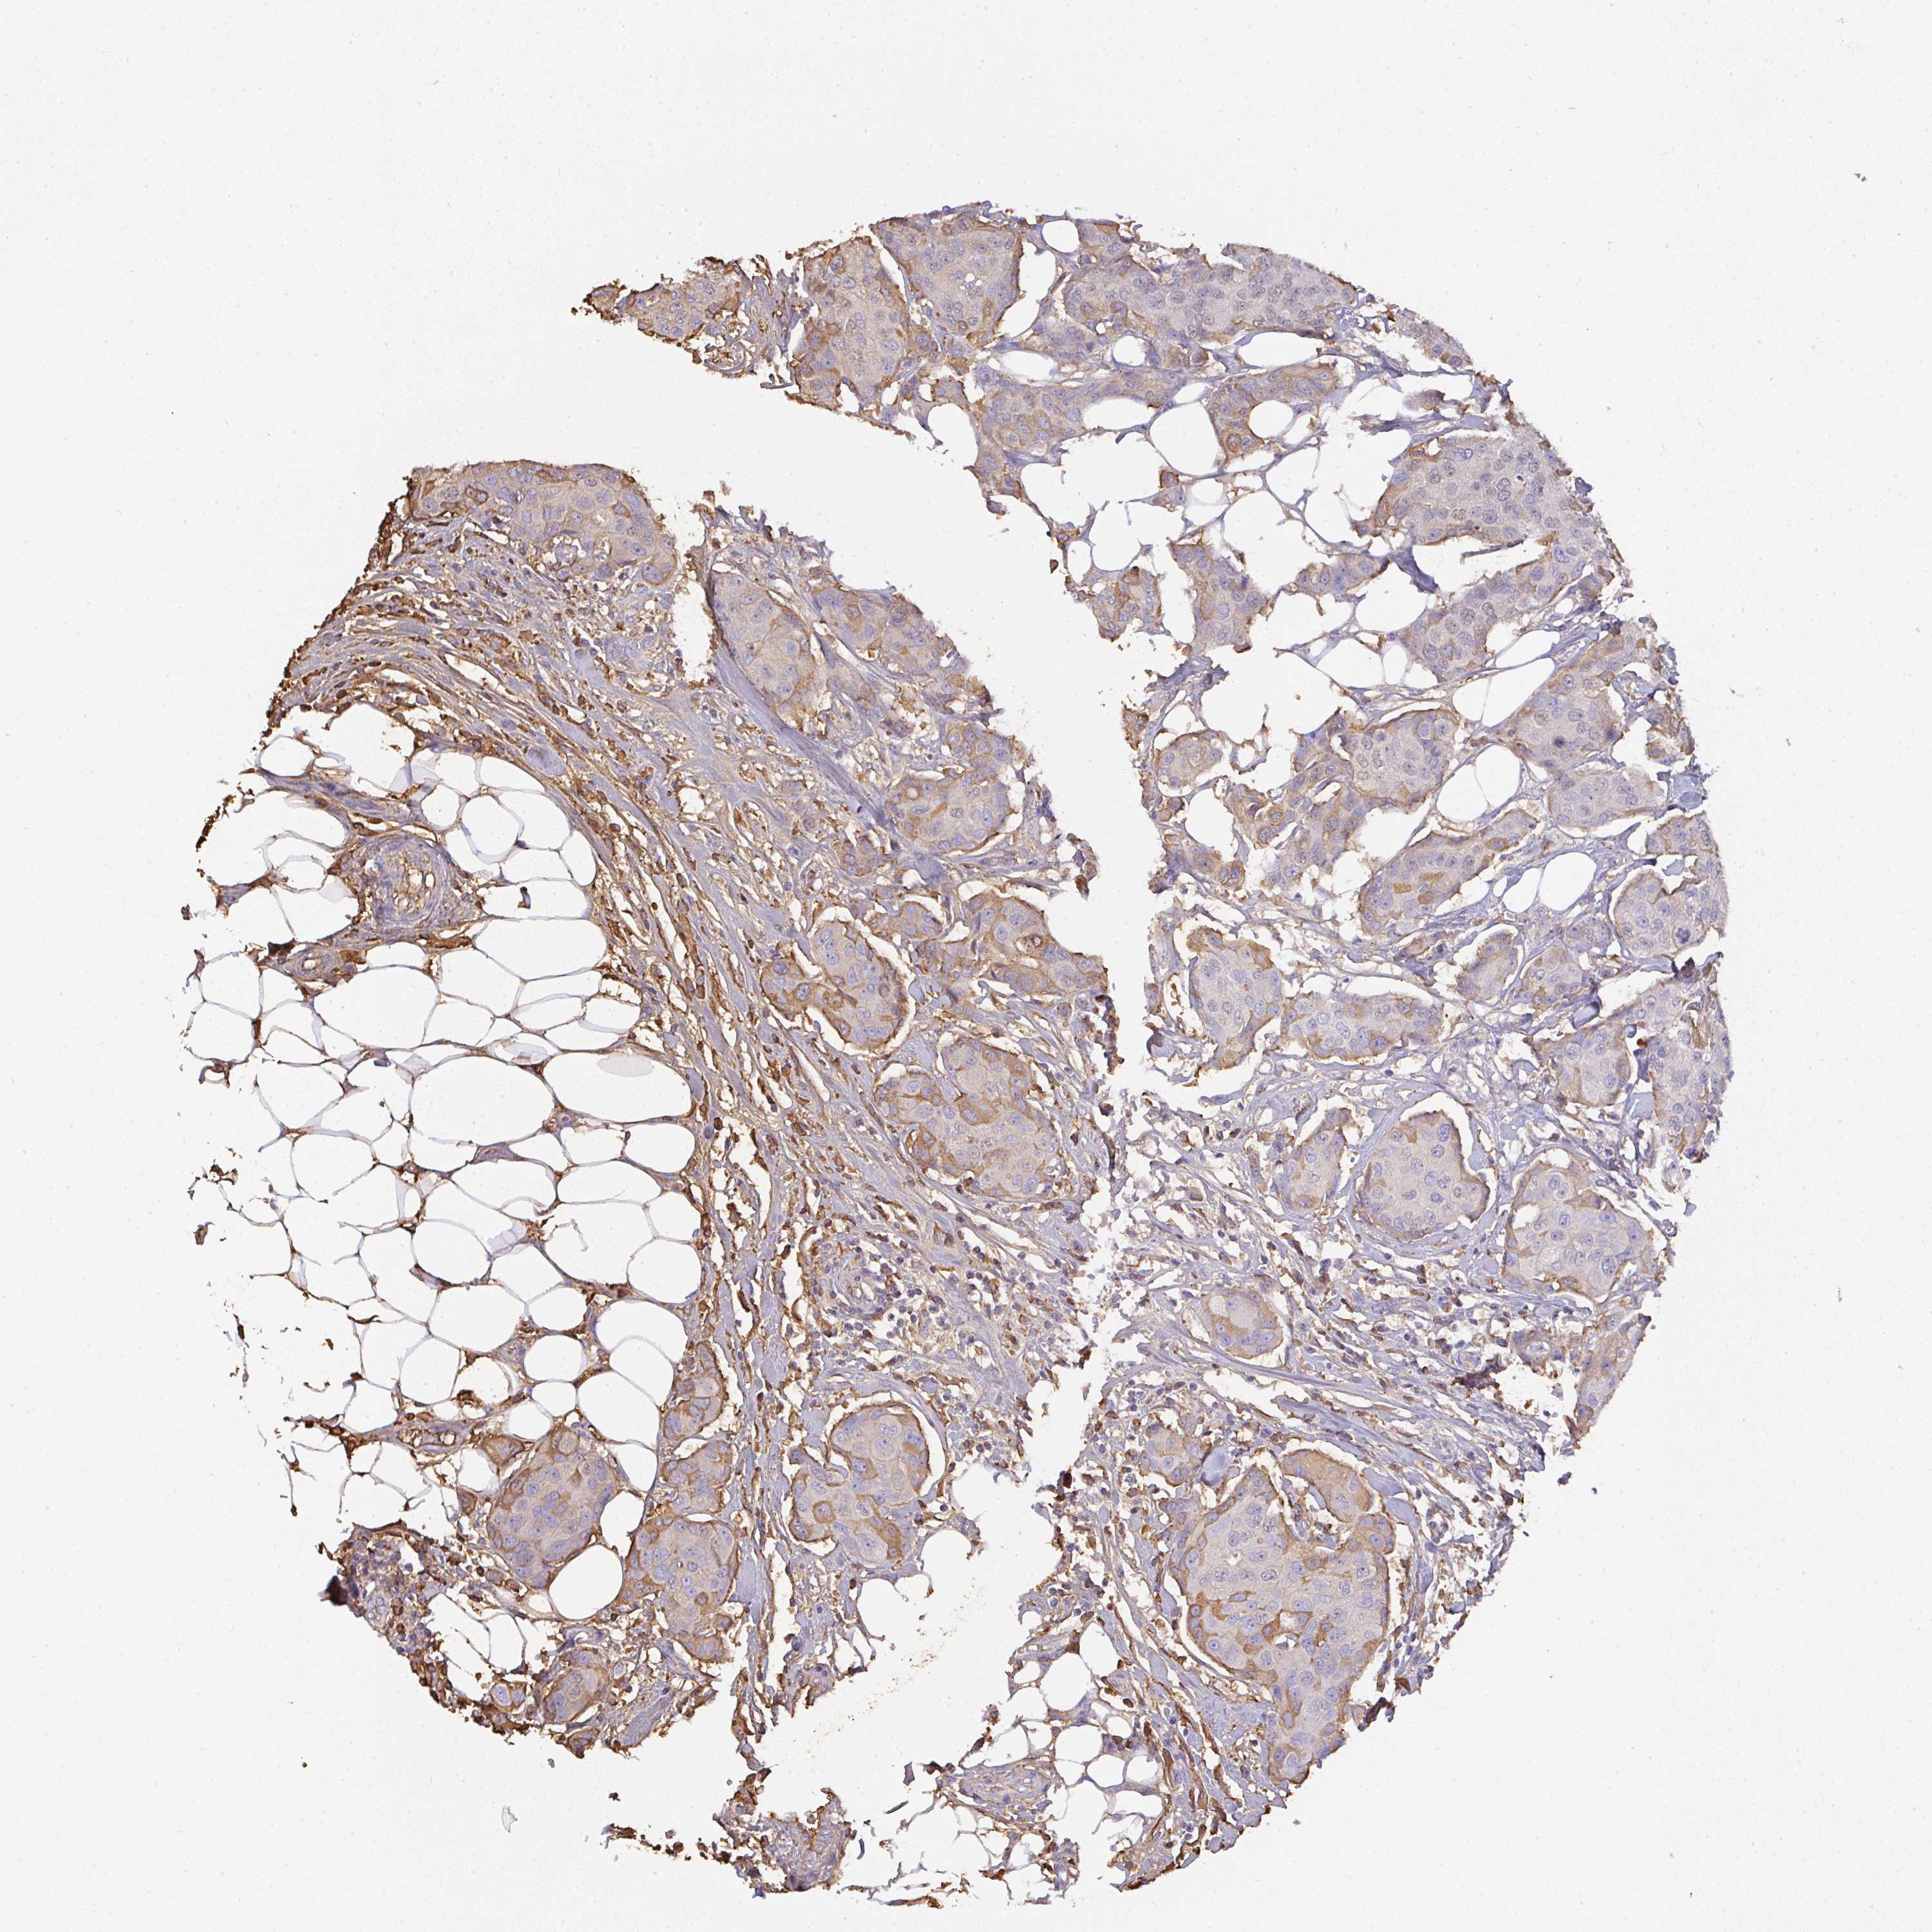

CANCER BREAST CANCER Show tissue menu

BRCA TCGA BRCA VALIDATION PROTEIN EXPRESSION

Breast cancer

Human cancer